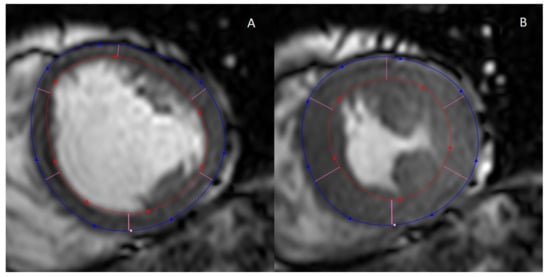

2.3. Myocardial Strain